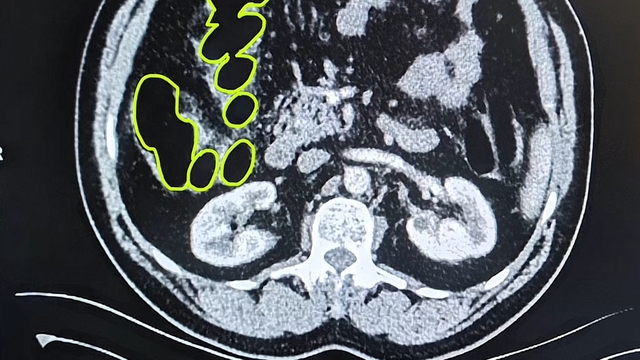

İl Jandarma Komutanlığı ekipleri, İran uyruklu A.O. (51), M.S. (37) ve P.S..'nin (28) ülkelerinden kente uyuşturucu getireceği bilgisine ulaştı. Şüpheliler Kocasinan ilçesi Himmetdede Mahallesi'nde taksi ile kente girmek istediği sırada durduruldu. Araçta yapılan aramada 15 gram esrar, 5 gram bonzai ve 117 adet uyuşturucu hap ele geçirildi. Gözaltına alınan 3 şüpheli muayene olmak üzere Kayseri Şehir Hastanesi'ne getirildi. Röntgen ve ultrason sonrası kontrollerde 3 şüphelinin midesinde uyuşturucu madde olduğu belirlendi. Şüphelilerin yuttukları uyuşturucuları kente sokmaya çalıştıkları tespit edildi. Kapsüller, sağlık ekibinin müdahalesiyle çıkarıldı. Taburcu edilen şüpheliler, İlçe Jandarma Komutanlığı'na götürüldü.